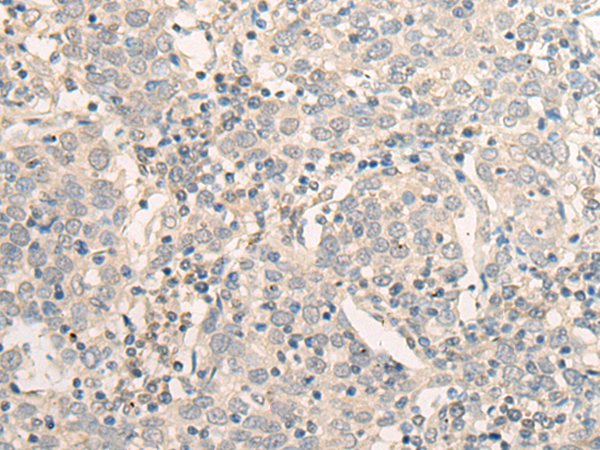

分类: 科研抗体货号: P09648别名:应用: WB,IHC反应种属: Human